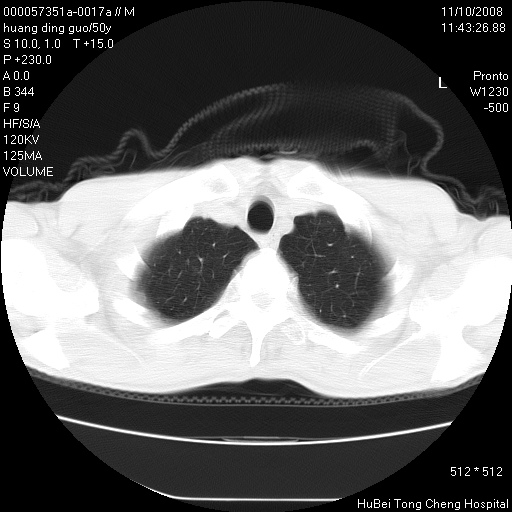

患者 男,50岁。左侧腰背部疼痛3月余,伴消瘦。平素健康,无传染病史。

胸部ct轴位平扫(层厚10mm,螺距1.5,重建间隔10mm),图像如下:

左肺下叶背段有一厚壁空洞,外壁呈锯齿状伴毛刺改变。空洞相邻胸膜有牵拉改变。左肺下叶血管支气管束不规则增粗,小叶间隔增厚。胸椎骨质破坏。考虑左肺下叶周围型肺癌伴左肺下叶癌性淋巴管炎、胸椎转移。

左肺下叶背段有一厚壁空洞,外壁呈锯齿状伴毛刺改变。空洞相邻胸膜有牵拉改变。左肺下叶血管支气管束不规则增粗,小叶间隔增厚。胸椎骨质破坏。考虑左肺下叶周围型肺癌伴阻塞性肺炎、胸椎转移。其他待排

左肺下叶背段有一厚壁空洞,内壁不规则,外壁呈锯齿状伴毛刺改变。空洞相邻胸膜有牵拉改变。周围呈絮状炎性改变,左肺下叶血管支气管束不规则增粗,小叶间隔增厚。胸椎骨质破坏。考虑左肺下叶周围型肺癌伴左肺下叶阻塞性肺炎、胸椎转移。